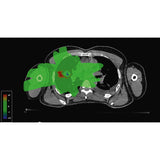

3D ANALYSIS VIA SLICE VIEWER

SciMoCa includes a slice viewer to visualize the TPS dose, SciMoCa-recalculated Monte Carlo dose, and Gamma analysis on individual CT slices. The 3D viewer permits detecting dose discrepancies on the patient anatomy level.